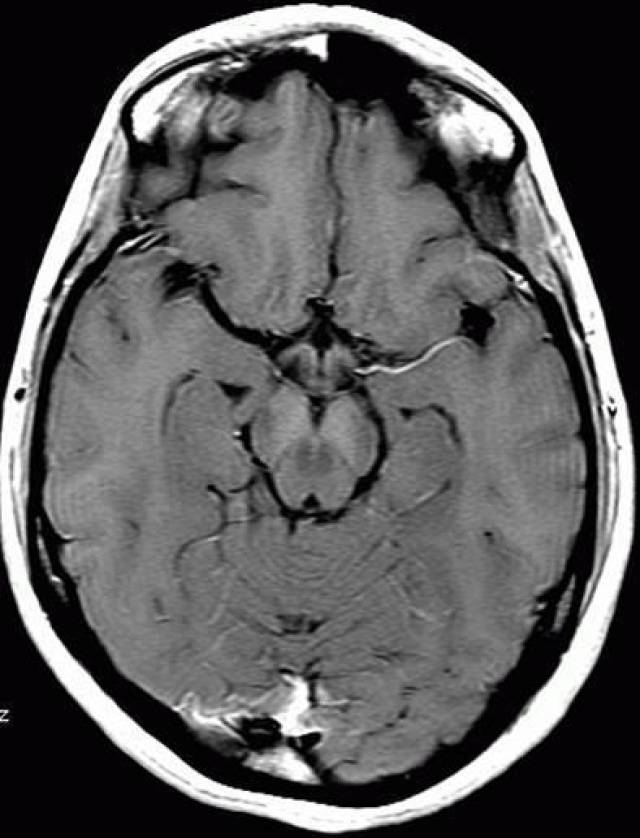

患者头颅磁共振成像未见异常